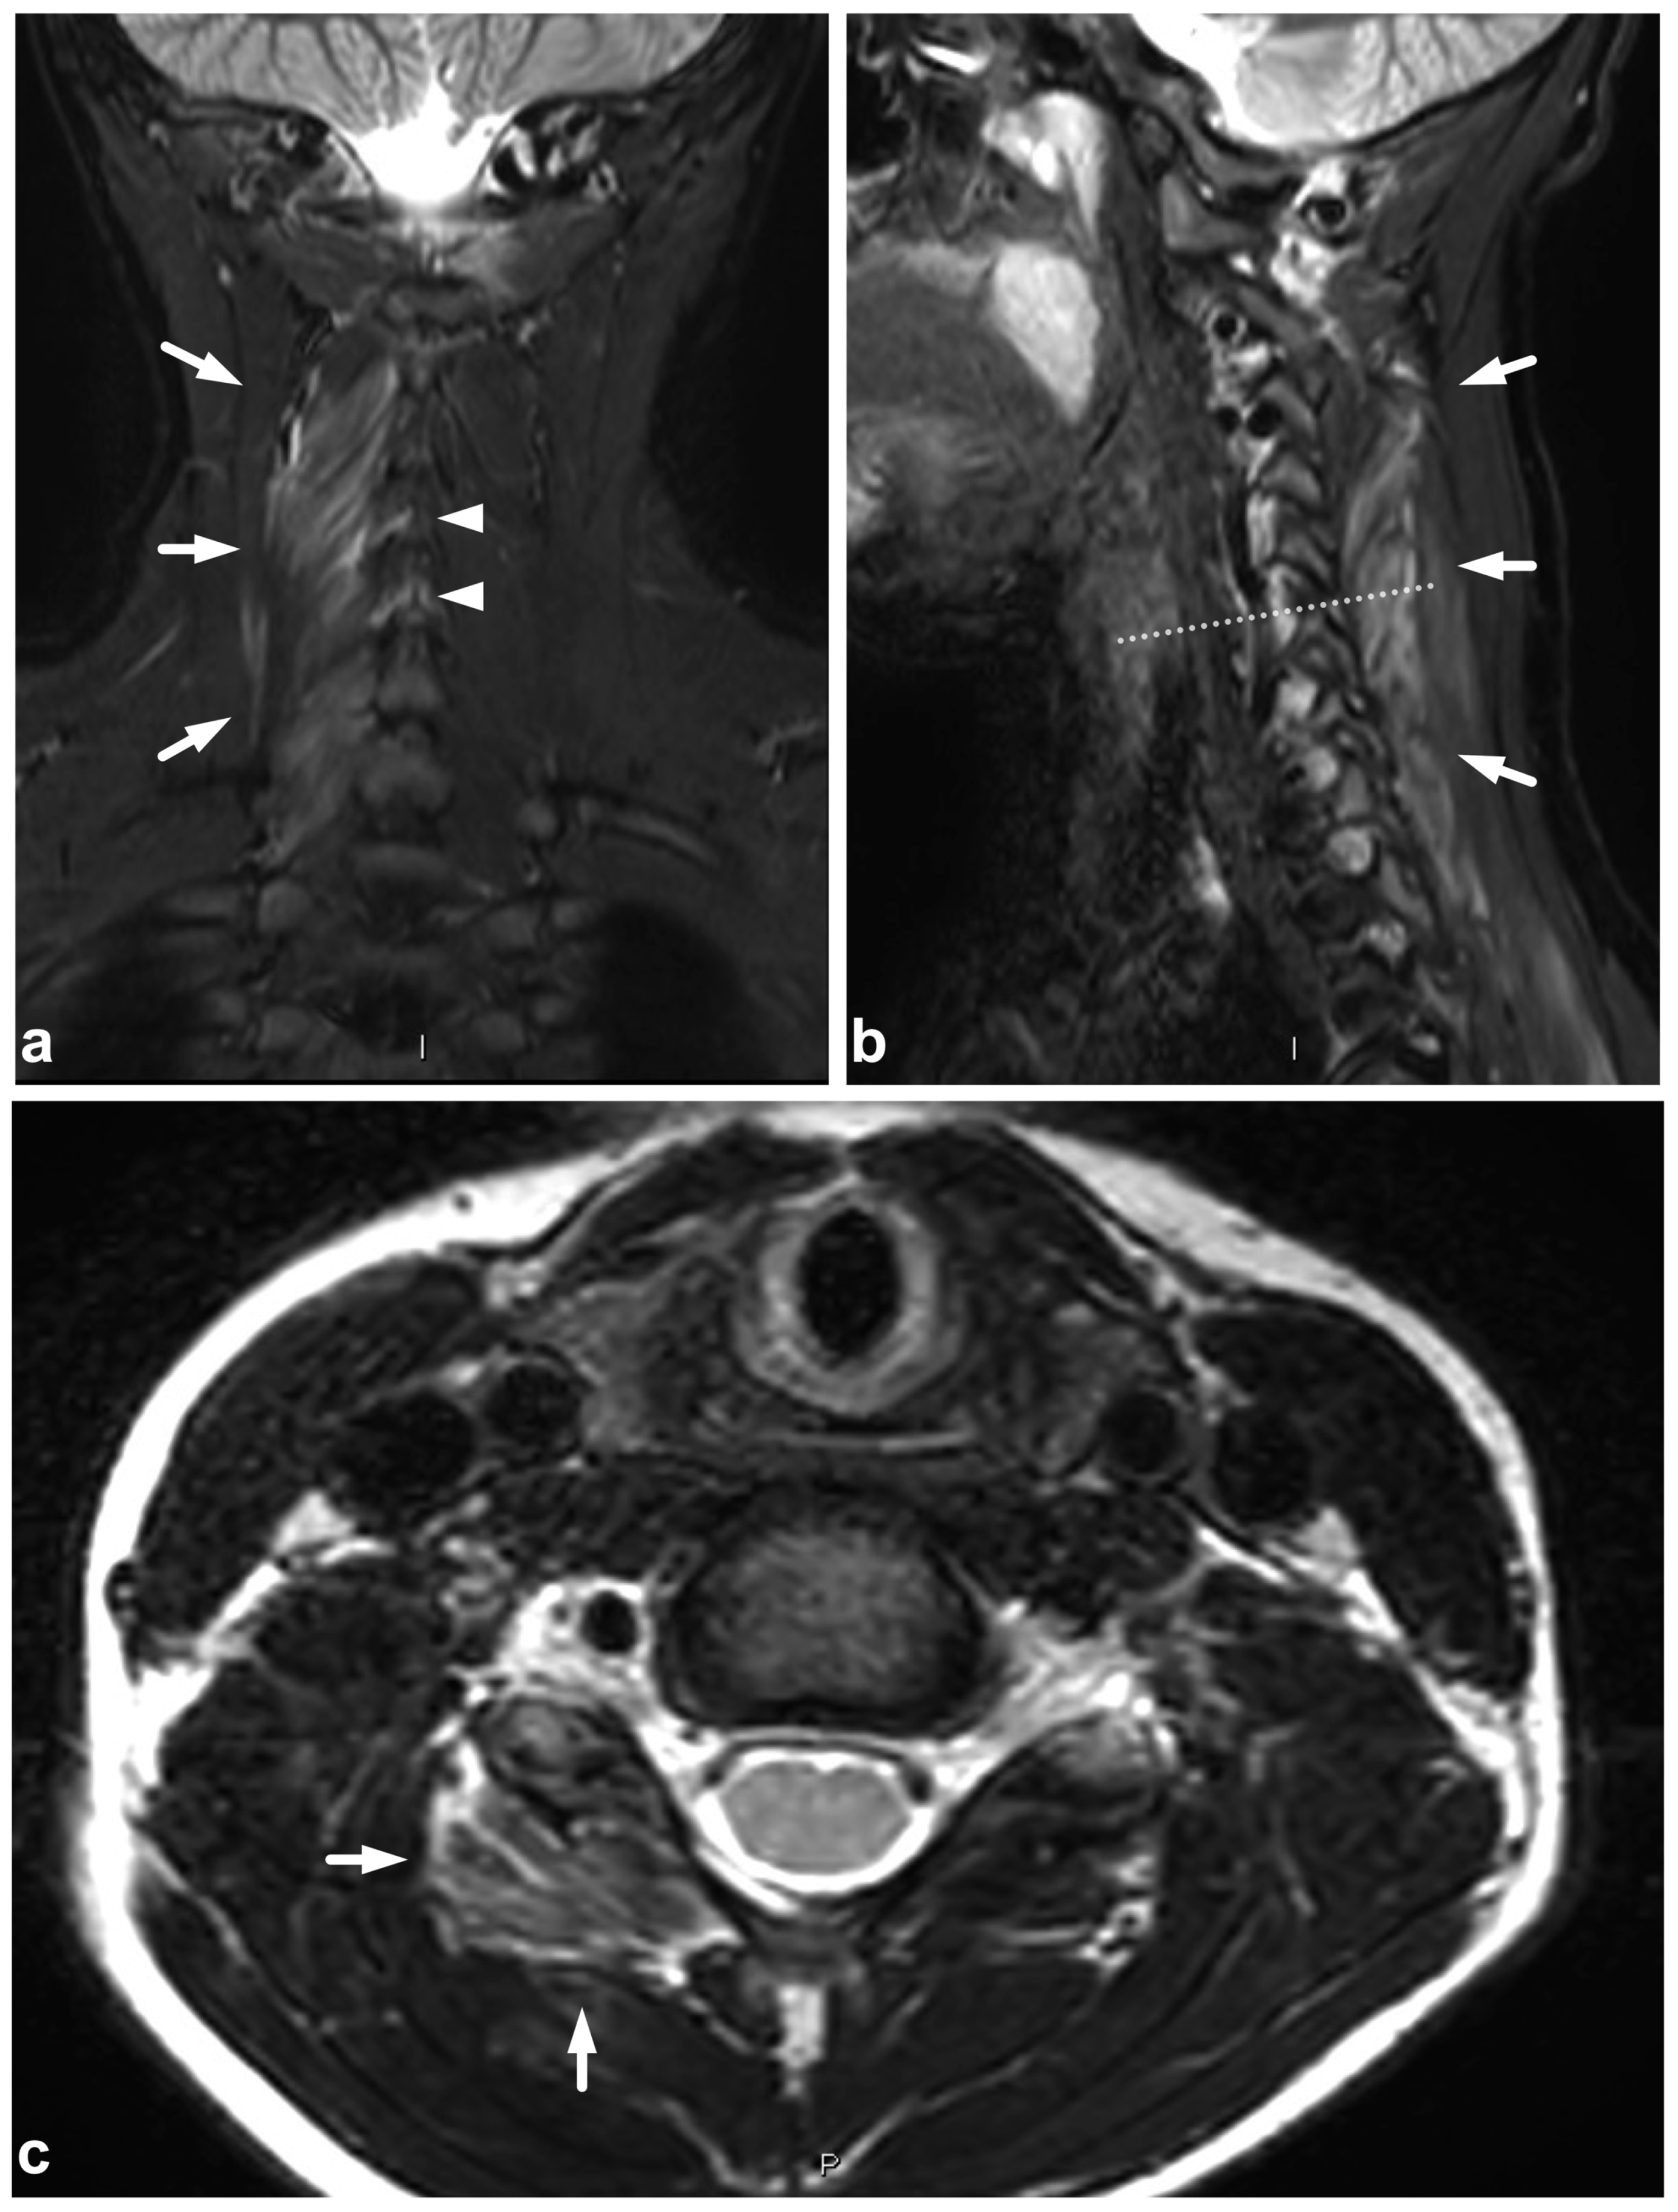

Figure 15.

(a) Sagittal T2-weighted. (b) Sagittal T1-weighted. (c) Sagittal T2-weighted fast field echo. (d) Coronal STIR. (e) Axial T2-weighted, level of the lower end plate of C6 (caudal dotted line in the image (b)). (f) Axial T1-weighted, level of the lower end plate of C6 (caudal dotted line in the image (b)). (g) Axial T2-weighted, level of the lower end plate of C5 (cranial dotted line in the image (b)). (h) Axial T1-weighted, level of the lower end plate of C5 (cranial dotted line in the image (b)). A 17-year-old male after diving into shallow water. The spinal cord is edematous approximately from the level of the lower end plate of C4 to the lower end plate of C6 (black arrowheads). There is a hemorrhagic contusion in the right-sided grey matter (white arrows) and a contusion without macroscopic hemorrhage on the left side (white arrowheads). Hematoma can be seen in the anterior epidural space (curved arrows). There are fractures of vertebral bodies and posterior arches of C5 and C6 (asterisks and small arrows).